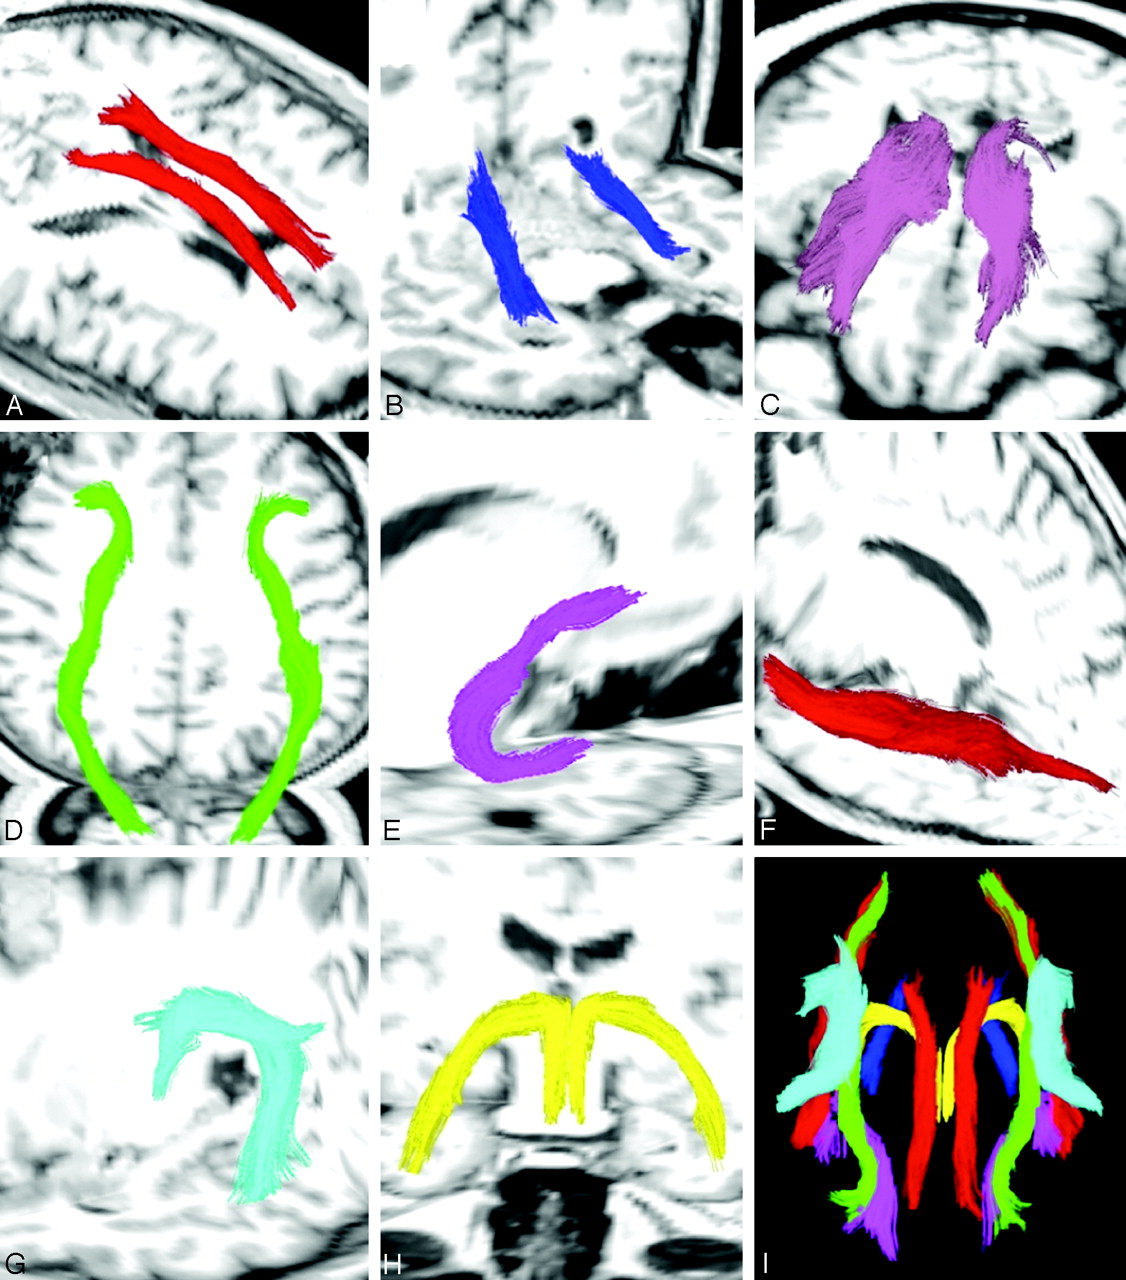

One rater (M.E.A.), who performed tracing of entire fiber tracts, was blinded to all clinical data, including group membership of subjects in control or patient groups and the side of the seizure focus. The following fiber tracts were traced (Fig 1): cingulum fibers within cingulate gyrus (CG), parahippocampal fibers within parahippocampal gyrus (PH), superior longitudinal fasciculus (SLF), inferior longitudinal fasciculus (ILF), UF, FORX, anterior thalamic radiations (ATR), and inferior fronto-occipital fasciculus (IFOF). The algorithms for obtaining most of the fiber tracts are described by Wakana et al.38 This multiple region of interest method uses “OR,” “AND,” and “NOT” operations to show all fiber tracts within a region of interest, find shared tracts within 2 regions of interest, and remove unnecessary fibers, respectively. This method has shown high reproducibility and was used to obtain the CG, PH, SLF, ILF, UF, ATR, and IFOF. However, the SLF and CG were slightly modified as follows: All SLF fiber tracts within the external capsule were removed by multiple “NOT” operations. For CG, “OR” regions of interest were drawn in the coronal plane in the region of CG at the level just posterior to the genu of the corpus callosum (CC) and anterior to the splenium of CC, with “AND” argument placed at the midpoint of CC (Fig 2A).

Traced fiber tracts in a control subject. A, Bilateral cingulum fibers within the CG. B, Bilateral PH. C, Bilateral ATR. D, Bilateral IFOF. E, Right UF. F, Left ILF. G, Left SLF. H, Bilateral FORX. I, Fibers in a 29-year-old control subject.